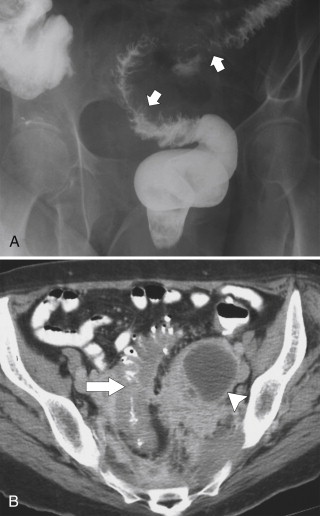

Plain radiography may demonstrate an ileus, sometimes confined to the left colon. As the disease progresses, bowel wall thickening develops ( Fig. 5-34 ) with a toxic megacolon if severe ( Fig. 5-35 ). BE is now rarely performed, but results demonstrate thickened folds and ulceration, either linear or with mucosal sloughing. Healing can lead to stricture formation ( Fig. 5-36 ). The findings are now usually made by CT and are similar to other forms of colitis (inflammatory bowel disease, infectious colitides, and radiation colitis if the radiation field included the colon). The disease is suggested in the appropriate clinical setting and by the left-sided distribution of the colonic changes ( Fig. 5-37 ). Severely affected patients show colonic pneumatosis as the gas permeates the damaged mucosa, which can then enter the mesenteric venous system and be recognized as mesenteric venous gas (particularly at CT) and ultimately intrahepatic portal venous gas. Occasionally, ischemia occurs proximal to an obstructing colonic stricture, such as colonic adenocarcinoma. The obstruction causes marked distention of the proximal colon, compromising its vascular supply or directly invading mesenteric vasculature ( Fig. 5-38 ).

Figure 5-38, A through C, Coronal and axial contrast-enhanced CT in a 62-year-old man with a transverse colon adenocarcinoma ( arrows ) with proximal ascending colon mucosal thickening due to secondary ischemia.